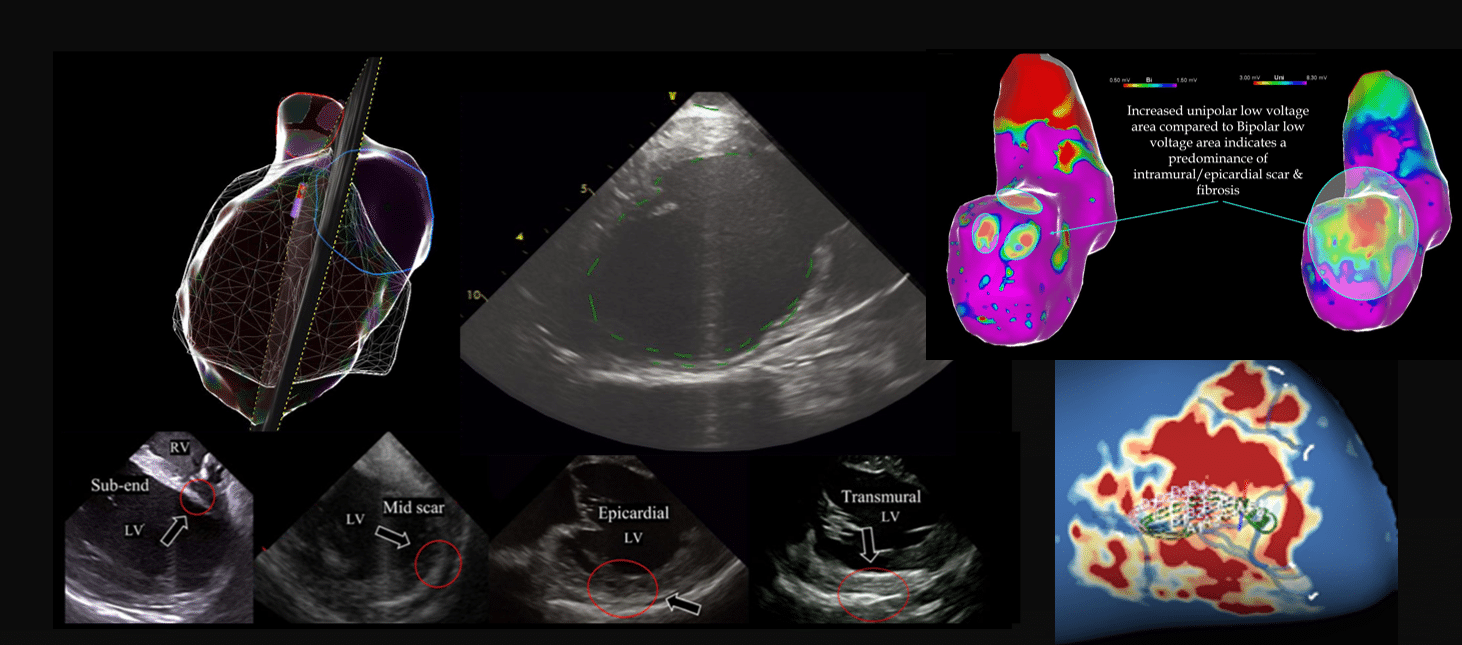

Bipolar Vs Unipolar mapping

• Unipolar voltages are sometimes used as a surrogate for identifying epicardial/intramural scar because Unipolar EGMS are influenced by the depolarisation amplitude of the full thickness of myocardium.

• Unipolar voltages are less dependent on wavefront direction with a wider field of view which may incorporate the full thickness of myocardial depolarisation.

• Scar anywhere within the thickness of myocardium should conceptually lower unipolar voltage.

What cut offs to use for LV unipolar voltage?

• Traditionally 3.3mV – 8.3mV.

• Based on data collected in 5 structurally normal patients where >95% of EGMs demonstrated unipolar amplitude >8.3mV, with a 4mm point-by point mapping (low density) without contact force.

Intracardiac Echo

• Regions of high echogenicity on Intracardiac Echo can also identify regions of scar.

• ICE has the advantage of identifying intramural & epicardial scar as well as endocardial scar.

• On ICE, myocardium that is thinned, akinetic, or has abnormal echo density can be delineated as scar, and has good correlation to scar defined by Electroanatomical mapping. These regions can be targeted for ablation.

images modified from: Kanawati J, De Silva K, Bhaskaran A, Turnbull S, Zhou J, Kotake Y, Kumar S, Campbell T. Intracardiac echocardiography techniques to identify ventricular arrhythmia substrate. Heart Rhythm O2. 2022 Jun 17;3(5):602-612.